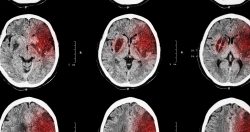

Tests that show images of the brain (CT scan, MRI), measure the brain’s electrical activity (EEG), and show blood flow to the brain (carotid duplex scan) are used to find out the type and severity of cerebrovascular disease.